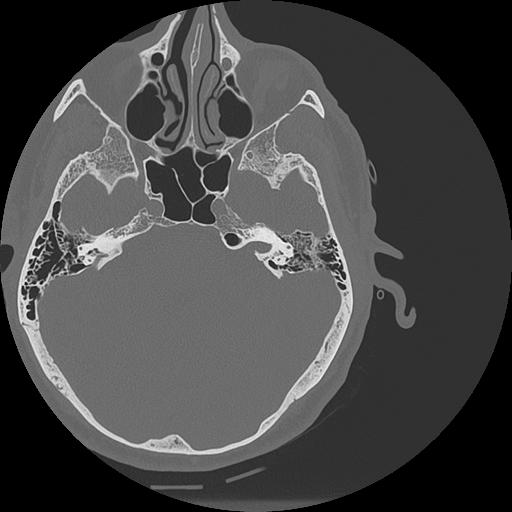

7 HUESO,,Vol,0.5,HUESO,,